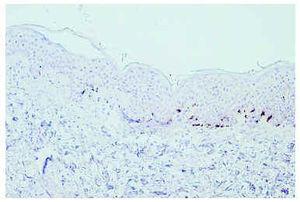

Caso 2. Varón de 28 años, diagnosticado en febrero de 2000 de un melanoma de extensión superficial en la región infraclavicular derecha, nivel III de 1,175 mm de espesor, asociado a una proliferación melanocítica benigna de apariencia congénita. Diez meses después se le realizó una linfadenectomía por una metástasis ganglionar supraclavicular derecha. Se inició tratamiento con IFN-α2b según el protocolo de Kirkwood, aunque fue necesario reducir la dosis al 50 % por la aparición de toxicidad hepática en la tercera semana. A los 5 meses de haber comenzado el tratamiento, aparecieron lesiones maculosas acrómicas asintomáticas en las regiones frontoparietales y frontotemporales. El estudio inmunohistoquímico de la biopsia de piel con Melan-A/Mart-1 mostraba una ausencia de diferenciación melanocítica en la piel afecta y la presencia de melanocitos basales en la piel sana (fig. 2). En noviembre de 2001 presentó una nueva metástasis supraclavicular derecha por lo que se le realizó disección cervical funcional y se añadió tratamiento con 6 ciclos mensuales de dacarbacina intravenosa. Terminó el tratamiento con IFN en mayo de 2002 y las lesiones cutáneas permanecieron estables. Durante el último ciclo de dacarbacina el paciente presentó metástasis cerebrales y falleció en junio de 2002, 28 meses después del diagnóstico.

Fig. 2.--Tinción con Melan A/MART-1 en la piel sana (derecha) y en la piel acrómica (izquierda). En la piel afectada existía una ausencia de diferenciación melanocítica y en la piel sana se observan los melanocitos basales.